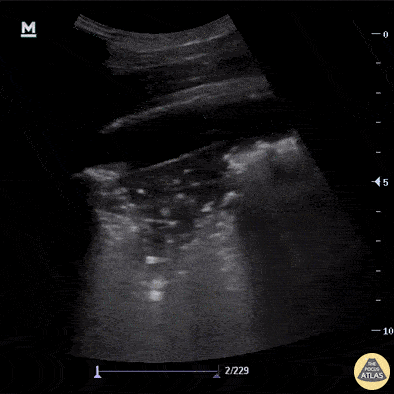

A 49-year-old with COPD and a 1-week history of cough and low-grade fever presents with worsening shortness of breath and right-sided pleuritic chest pain after a prolonged coughing fit. Vitals: T 37.8°C, HR 116, BP 132/78, RR 28, SpO₂ 90% on room air. Exam: mild respiratory distress, decreased breath sounds at the right apex, scattered expiratory wheeze, and a few coarse right-sided crackles. Right lung pocus is shown. Describe the findings. What is the diagnosis?

What is lung point?

Diagnosis: Pneumothorax